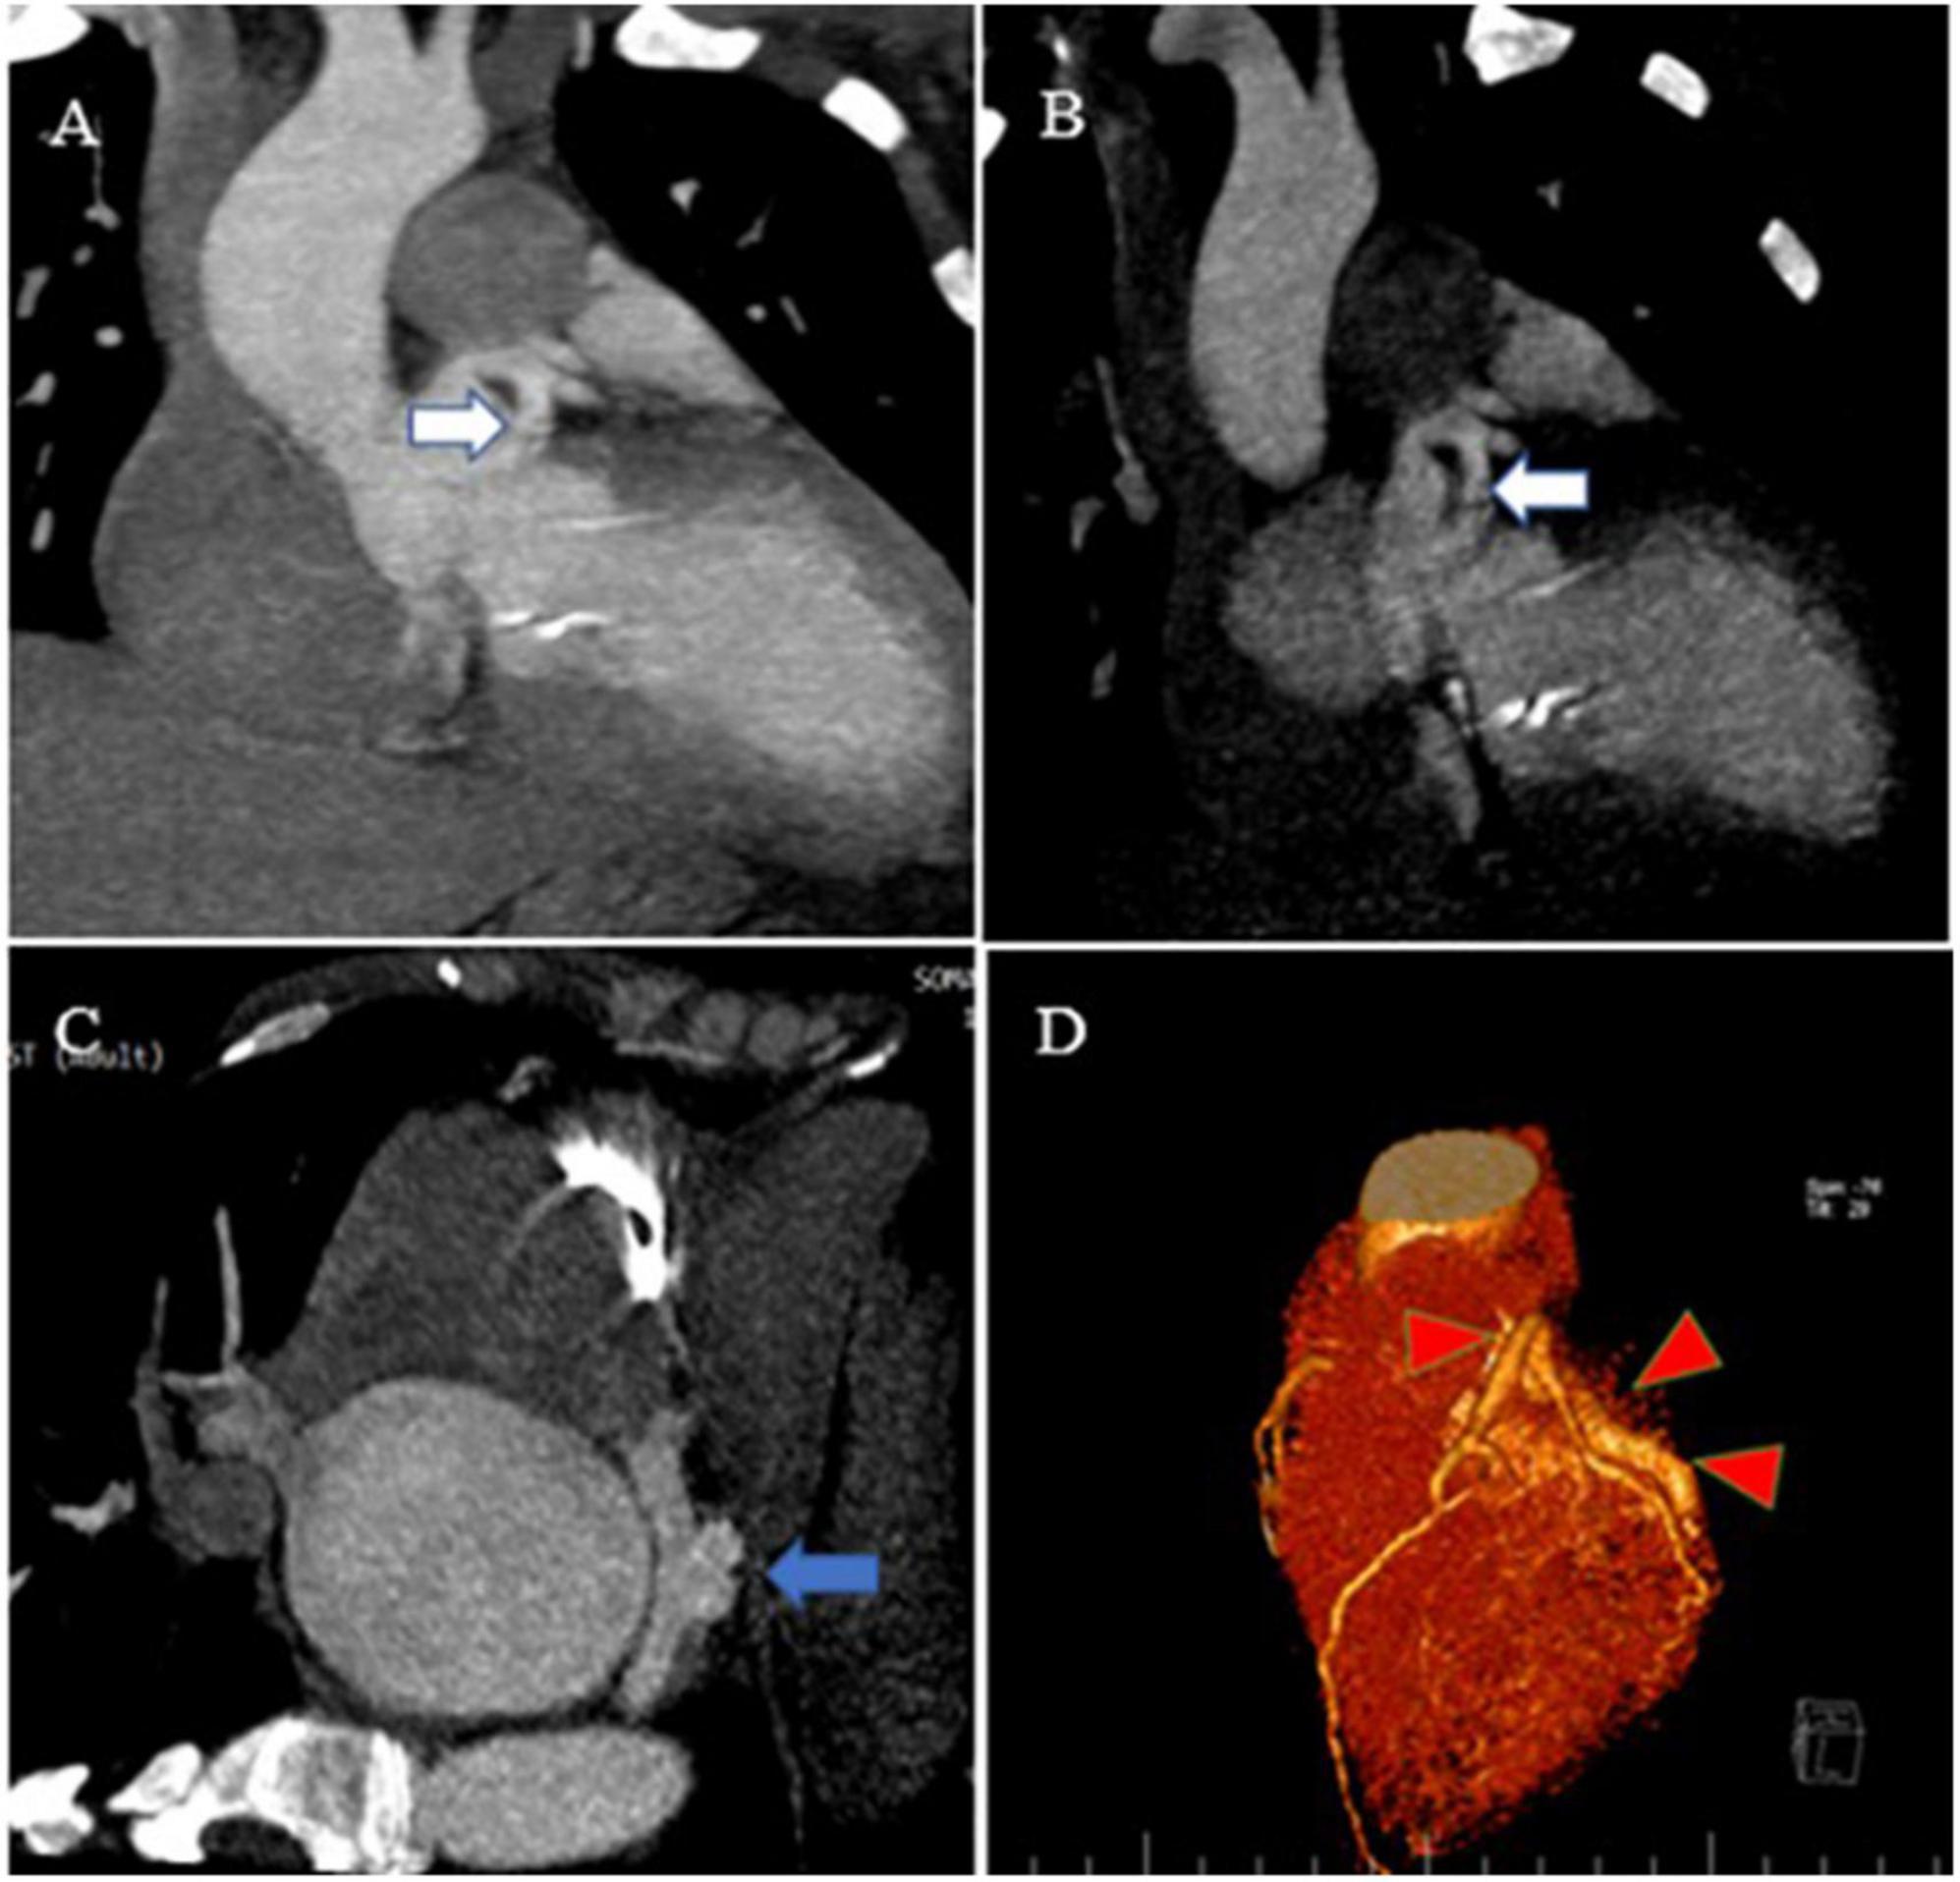

FIGURE 3

Contrast-enhanced CT scan of the chest, as well as CCTA, show the proximal site of a giant fistula originating from the left circumflex artery (white arrow), draining into the coronary sinus and forming a pouch (blue arrow). Reconstruction of coronaries illustrates a giant fistula (red color arrowheads).